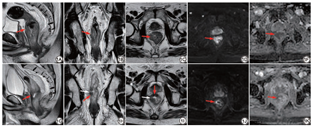

单独采用T2WI序列进行评估,mrTRG 1~2级57例,3~5级72例。采用T2WI联合DWI序列进行评估,mrTRG 1~2级70例,3~5级59例。病理评估结果显示,pTRG 0~1级66例,pTRG 2~3级63例。mrTRG与pTRG间总体一致性中等(单纯T2WI:Kappa=0.602,P<0.001;T2WI+DWI:Kappa=0.693,P<0.001)。与单纯应用T2WI序列相比,T2WI联合DWI提高了mrTRG的敏感度(86.4% vs. 82.9%)、特异度(83.9% vs. 77.1%)、阴性预测值(89.7% vs. 79.4%)、约登指数(70.3% vs. 60.0%)、总符合率(84.9% vs. 80.2%)(图1)。因此,下文中评估不同因素对mrTRG诊断效能的影响选用mrTRG(T2WI+DWI)。

DWI能反映组织结构微观水平的变化,能够对残余肿瘤活性进行评估。残余肿瘤在DWI图中表现为高信号,在纤维瘢痕低信号背景中更容易发现。既往大量研究发现DWI可提高mrTRG的观察者间一致性和准确性[12, 13, 14, 15]。而且,通过测量ADC值,能定量评估肿瘤的病理变化,预测直肠癌nCRT的疗效,尤其对病理完全缓解具有较高的预测价值[16, 17, 18, 19, 20]。本研究结果显示,T2WI联合DWI可提高mrTRG与pTRG间的总体一致性。与单纯应用T2WI相比,T2WI联合DWI显著提高了mrTRG的敏感度、特异度、阴性预测值、约登指数、总符合率,与上述研究相符。DWI能够提升mrTRG的诊断效能,推荐作为直肠癌nCRT后MR检查的常规扫描序列。